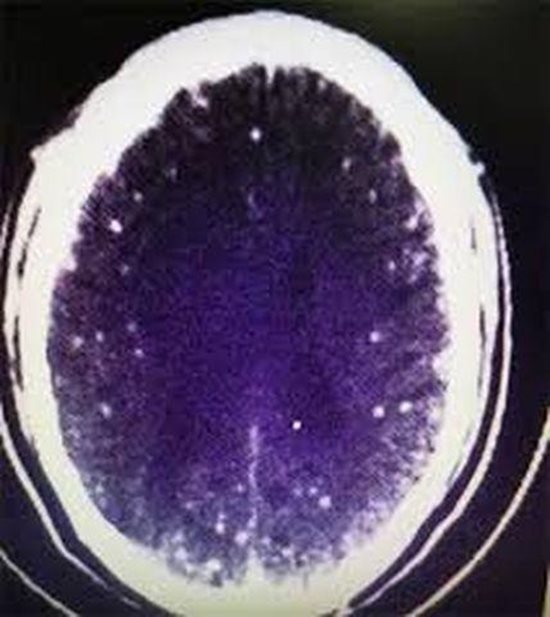

Các bác sĩ sau khi chụp CT não thấy “có nhiều vôi hóa nội sọ”, cộng hưởng từ đầu cho thấy nhiều tổn thương nội sọ. Bệnh viện địa phương đề nghị kiểm tra và xác nhận thêm. Tuy nhiên, do cảm thấy bản thân đã khỏe hơn và sợ tốn tiền nên ông Châu từ chối.

Biết ông Châu đã ăn lẩu thịt cừu thịt lợn trước đây không lâu, bác sĩ đã đề nghị chụp cộng hưởng từ não, kết quả cho thấy có nhiều tổn thương ở 2 bên bán cầu não, kết hợp kết quả kháng thể ấu trùng trong máu và não tủy dương tính, chẩn đoán là bệnh sán não.

Ảnh chụp X quang phát hiện não của ông Chu có nhiều vôi hóa. |